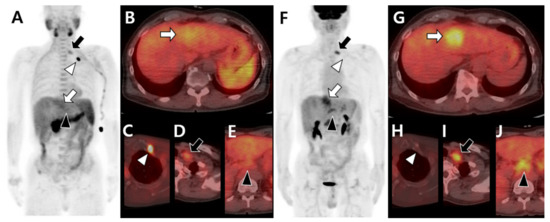

- Ho, C.L.; Chen, S.; Cheng, T.K.; Leung, Y.L. PET/CT characteristics of isolated bone metastases in hepatocellular carcinoma. Radiology 2011, 258, 515–523. [Google Scholar] [CrossRef] [PubMed]

- Yoo, S.W.; Kim, D.Y.; Pyo, A.; Jeon, S.; Kim, J.; Kang, S.R.; Cho, S.G.; Lee, C.; Kim, G.J.; Song, H.C.; et al. Differences in diagnostic impact of dual-tracer PET/computed tomography according to the extrahepatic metastatic site in patients with hepatocellular carcinoma. Nucl. Med. Commun. 2021, 42, 685–693. [Google Scholar] [CrossRef] [PubMed]

- Ho, C.L.; Chen, S.; Yeung, D.W.; Cheng, T.K. Dual-tracer PET/CT imaging in evaluation of metastatic hepatocellular carcinoma. J. Nucl. Med. 2007, 48, 902–909. [Google Scholar] [CrossRef]